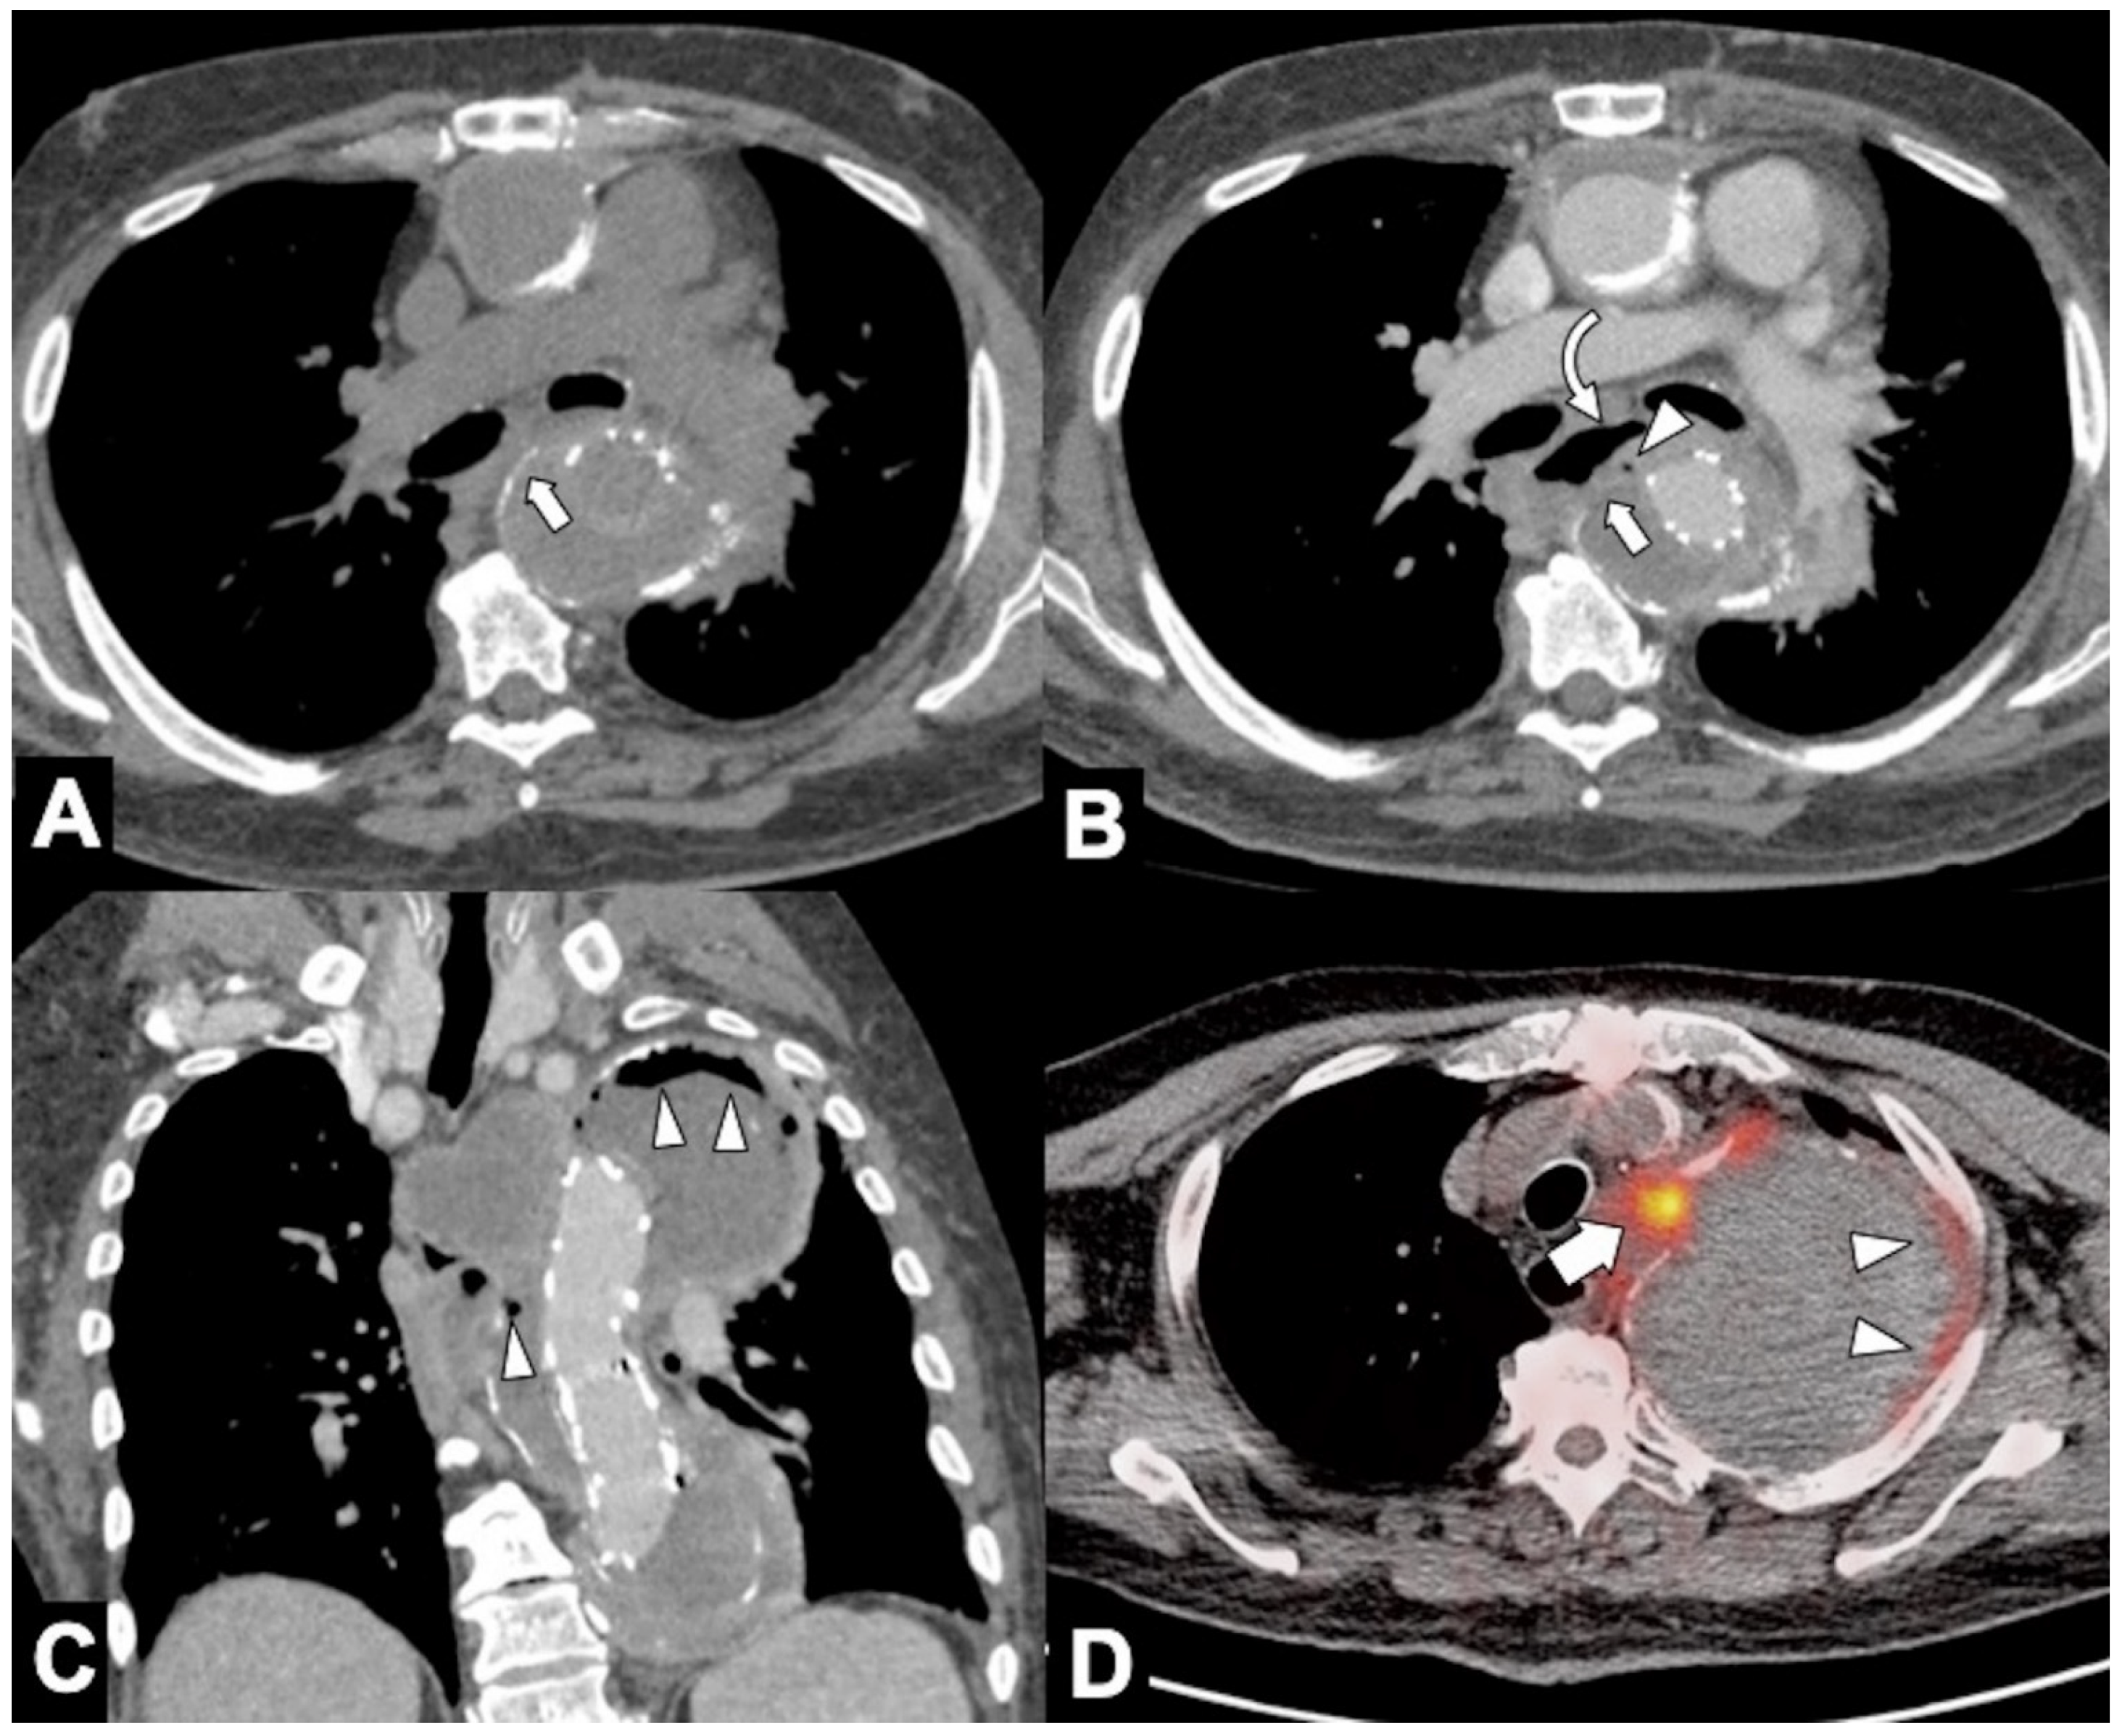

Figure 13. CT evaluation and CT-PET in a 68-year-old male patient with an aortoesophageal fistula (AEF) after 28 days from TEVAR. (A,B) CTA evaluation for the onset of fever showing disappearance of thoracic descending aortic wall calcification (arrow), distended esophagus (curved arrow), and appearance of an ectopic small air bubble in the native aneurysmal aortic lumen (arrowhead). (C) Coronal oblique MPR image better shows a significant amount of air in the native aortic lumen (arrowheads) due to probable AEF. (D) Fused FDG PET-CT axial image shows multiple foci of increased FDG uptake both in the aneurysm wall (arrowheads) both in the mediastinum (arrow) suggestive of infected thoracic aortic aneurysm and TEVAR endograft.